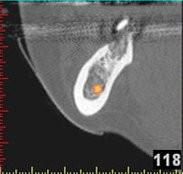

In komplexen Fällen, z. B. der Implantatversorgung eines kompletten Kiefers, oder bei schwierigen Knochensituationen bietet die 3-dimensionale Computerdiagnostik bzw. Planung und Durchführung erhebliche Vorteile und Sicherheit für den Patienten (siehe Bild 1 und 2).

Auf Basis einer computertomografischen (CT-) Kieferaufnahme ist eine dreidimensionale Darstellung der Knochen möglich. Der Zahnarzt kann dann am Computerbildschirm die Knochenqualität (z. B. Knochendichte) beurteilen und die optimale Position der Implantate im Vorfeld planen. Durch Verwendung spezieller Röntgenschablonen lässt sich auch die erwünschte Zahnstellung in die Planung einbeziehen. Die Simulation der OP erlaubt, das zu erwartende Ergebnis mit größtmöglicher Sicherheit vorherzusagen und dem Patienten am Bildschirm zu veranschaulichen.